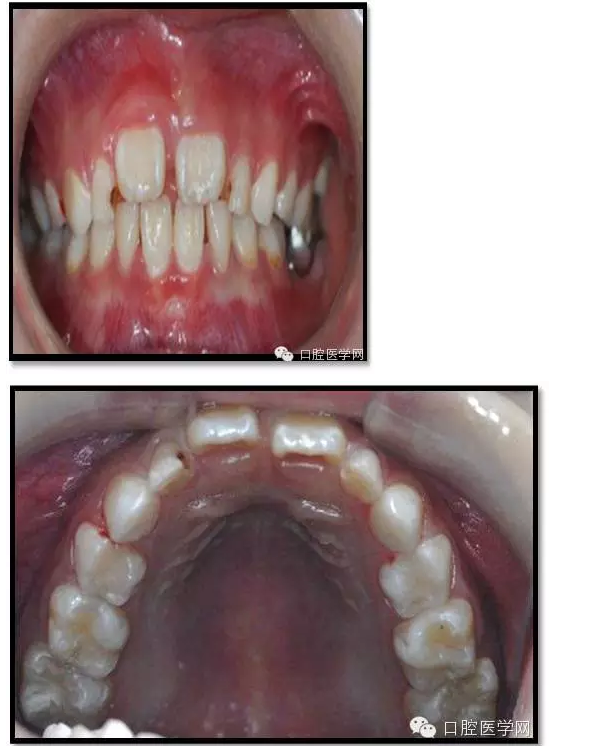

檢查:口腔衛(wèi)生一般,牙面軟垢菌斑中量。 85O、84DO充填完好,邊緣密合,叩(-),不松,齦無紅腫。

75帶環(huán)絲圈式間隙保持器完好,無松動,無咬合不適。

余牙充填體完好密合,未查及繼發(fā)齲和新發(fā)齲壞。

治療結(jié)束后7個月復(fù)查

85O、84DO充填完好,邊緣密合,叩(-),不松,齦無紅腫。X線:84、85根分歧透射影,44、45骨硬板連續(xù),恒牙胚上方骨板厚約2-3mm。75帶環(huán)絲圈式間隙保持器完好,無松動,無咬合不適。64MO中齲。 64MO中齲去腐凈,自酸蝕,SEBOND,樹脂充填。 口腔衛(wèi)生宣教,囑3個月后復(fù)診。